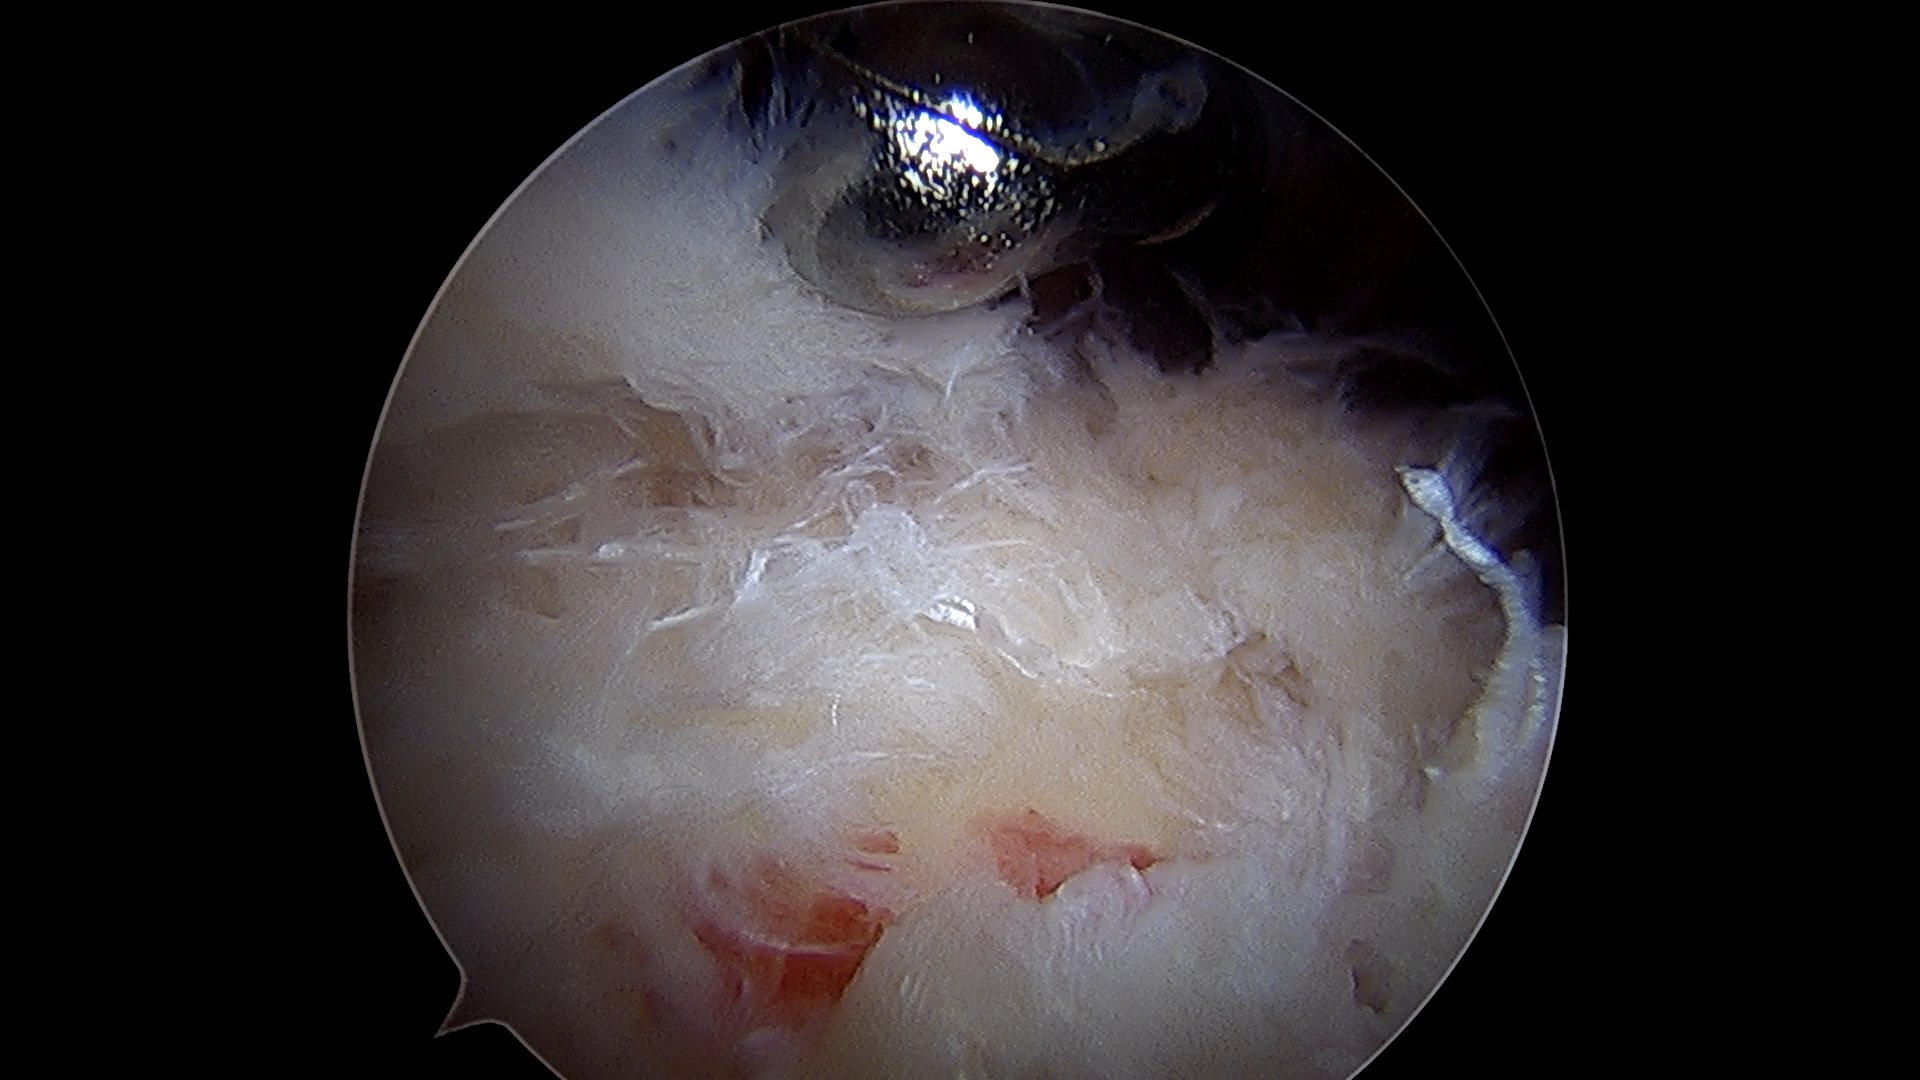

동종진피 이식술은 관절내시경을 이용해

찢어진 회전근개 부위에 동종진피를 덧대어

힘줄을 보강하는 수술 방법입니다.